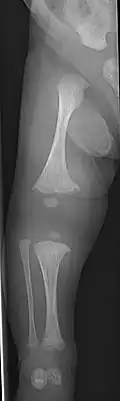

Diagnosis is typically based on medical imaging, including plain X-rays, and symptoms. In severe OI, signs on medical imaging include abnormalities in all extremities and the spine.[97] As X-rays are often insensitive to the comparatively smaller bone density loss associated with type I OI, DEXA scans may be needed.[5]: 1514

An OI diagnosis can be confirmed through DNA or collagen protein analysis, but in many cases, the occurrence of bone fractures with little trauma and the presence of other clinical features such as blue sclerae are sufficient for a diagnosis. A skin biopsy can be performed to determine the structure and quantity of type I collagen. While DNA testing can confirm the diagnosis, it cannot absolutely exclude it because not all mutations causing OI are yet known and/or tested for.[83]: 491–492 OI type II is often diagnosed by ultrasound during pregnancy, where already multiple fractures and other characteristic features may be visible. Relative to control, OI cortical bone shows increased porosity, canal diameter, and connectivity in micro-computed tomography.[98] OI can also be detected before birth by using an in vitro genetic testing technique such as amniocentresis.[99]